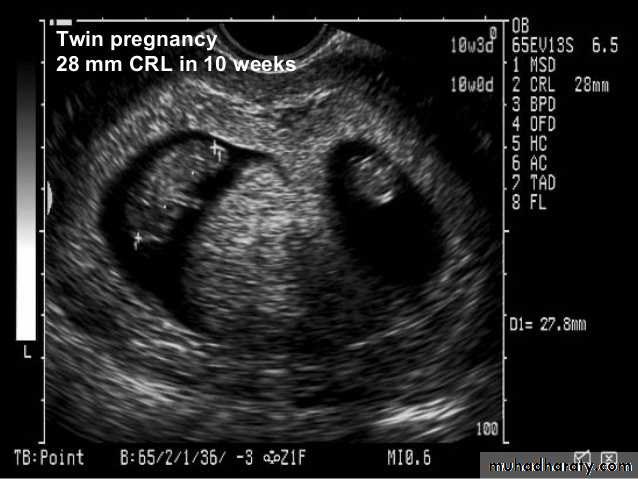

US of the obstetric & Gyne.BPD together with head circumference (HC), abdominal circumference (AC), and femur length (FL) are computed to produce an estimate of fetal weight. In the second trimester this may be extrapolated to an estimate of gestational age and an estimated due date (EDD) .